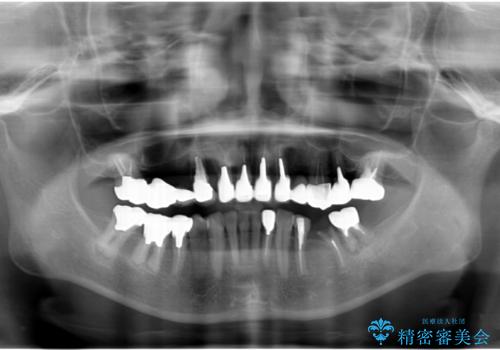

全顎的 虫歯治療 インプラント補綴

- 「他院で虫歯治療を行っているが、延々終わらず数年経過している。全体的な治療を希望したい。」と全顎的な治療を希望され来院されました。

・再発した虫歯

・銀歯の下にできた虫歯

・根尖性歯周炎

・残根状態の歯

など、虫歯を原因とする問題が多発した状態です。

今後延々と治療を繰り返さないために、全ての銀歯を外し虫歯を丁寧に取り切り、根管治療を行い、残せない歯は抜去を行った上でインプラント治療を行っていくことで全体的な治療を計画していくこととなりました。